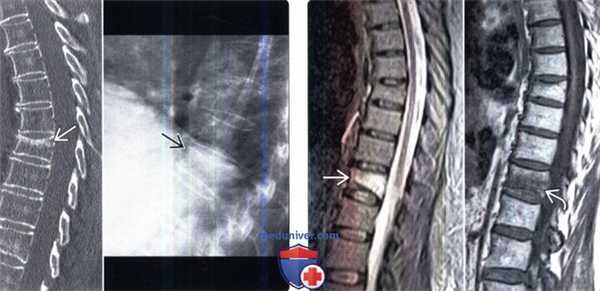

(Слева) МРТ Т2ВИ, сагиттальный срез: плотные тяжи с четкими границами и низкой интенсивностью сигнала, обусловленной склерозом кости с поражением тел всех позвонков. Такая МР-картина соответствует синдрому «джемпера регбиста». Обратите внимание на то, что склероз и утолщение трабекул также имеются в центральной части тел позвонков.

(Справа) Рентгенография в боковой проекции: в этом случае у пациента с младенческим остеопетрозом во всех костных структурах, включая тела позвонков, нервные дуги и ребра, определяется выраженное диффузное уплотнение кости за счет склероза. (Слева) На увеличенной рентгенограмме позвонка L4 в боковой проекции определяется классическая картина по типу «кость в кости».

(Справа) КТ, костное окно, аксиальный срез: картина позвонка по типу «кость в кости». Обратите внимание на то, что форма визуализируемого склерозированного образования точно соответствует краям кортикального слоя. (Слева) Рентгенография в ПЗ проекции: пациент с остеопетрозом, осложненным подвертельным переломом. Обратите внимание на внутреннюю кость крыла подвздошной кости и характерное утолщение кортикального слоя бедренной кости.